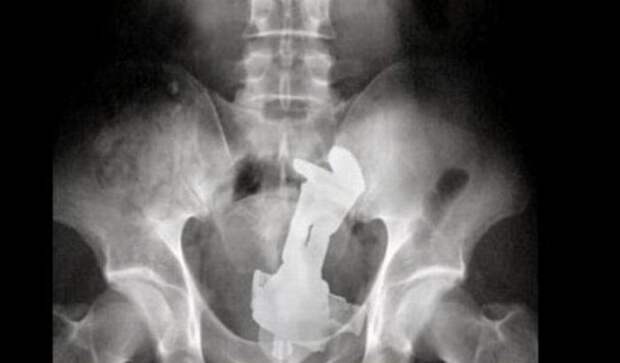

4. ДЕЗОДОРАНТ – НУЖНО ПРИЯТНО ПАХНУТЬ!

Дезодорант – один из необходимых средств для человека, чтобы приятно пахнуть и оставаться свежим в течение всего дня. Мы всегда хотим произвести впечатление на тех, кто вокруг нас и важное значение имеет запах тела. Поэтому, не удивительно, что в одном из самых жарких мест мира, Саудовской Аравии человек должен иметь дезодорант. Удивительно было тогда, когда человек поступил в больницу Эр-Рияд с болью в нижней части живота и рентген показал целую баночку аэрозоля в прямой кишке.

23-летнему пациенту было нечего сказать о самовведении дезодоранта, и он смущенно сбежал после того, как врачи наполовину вручную удалили предмет. Один совет, чувак, в следующий раз используй дезодорант Axe. Эта баночка гораздо меньше.